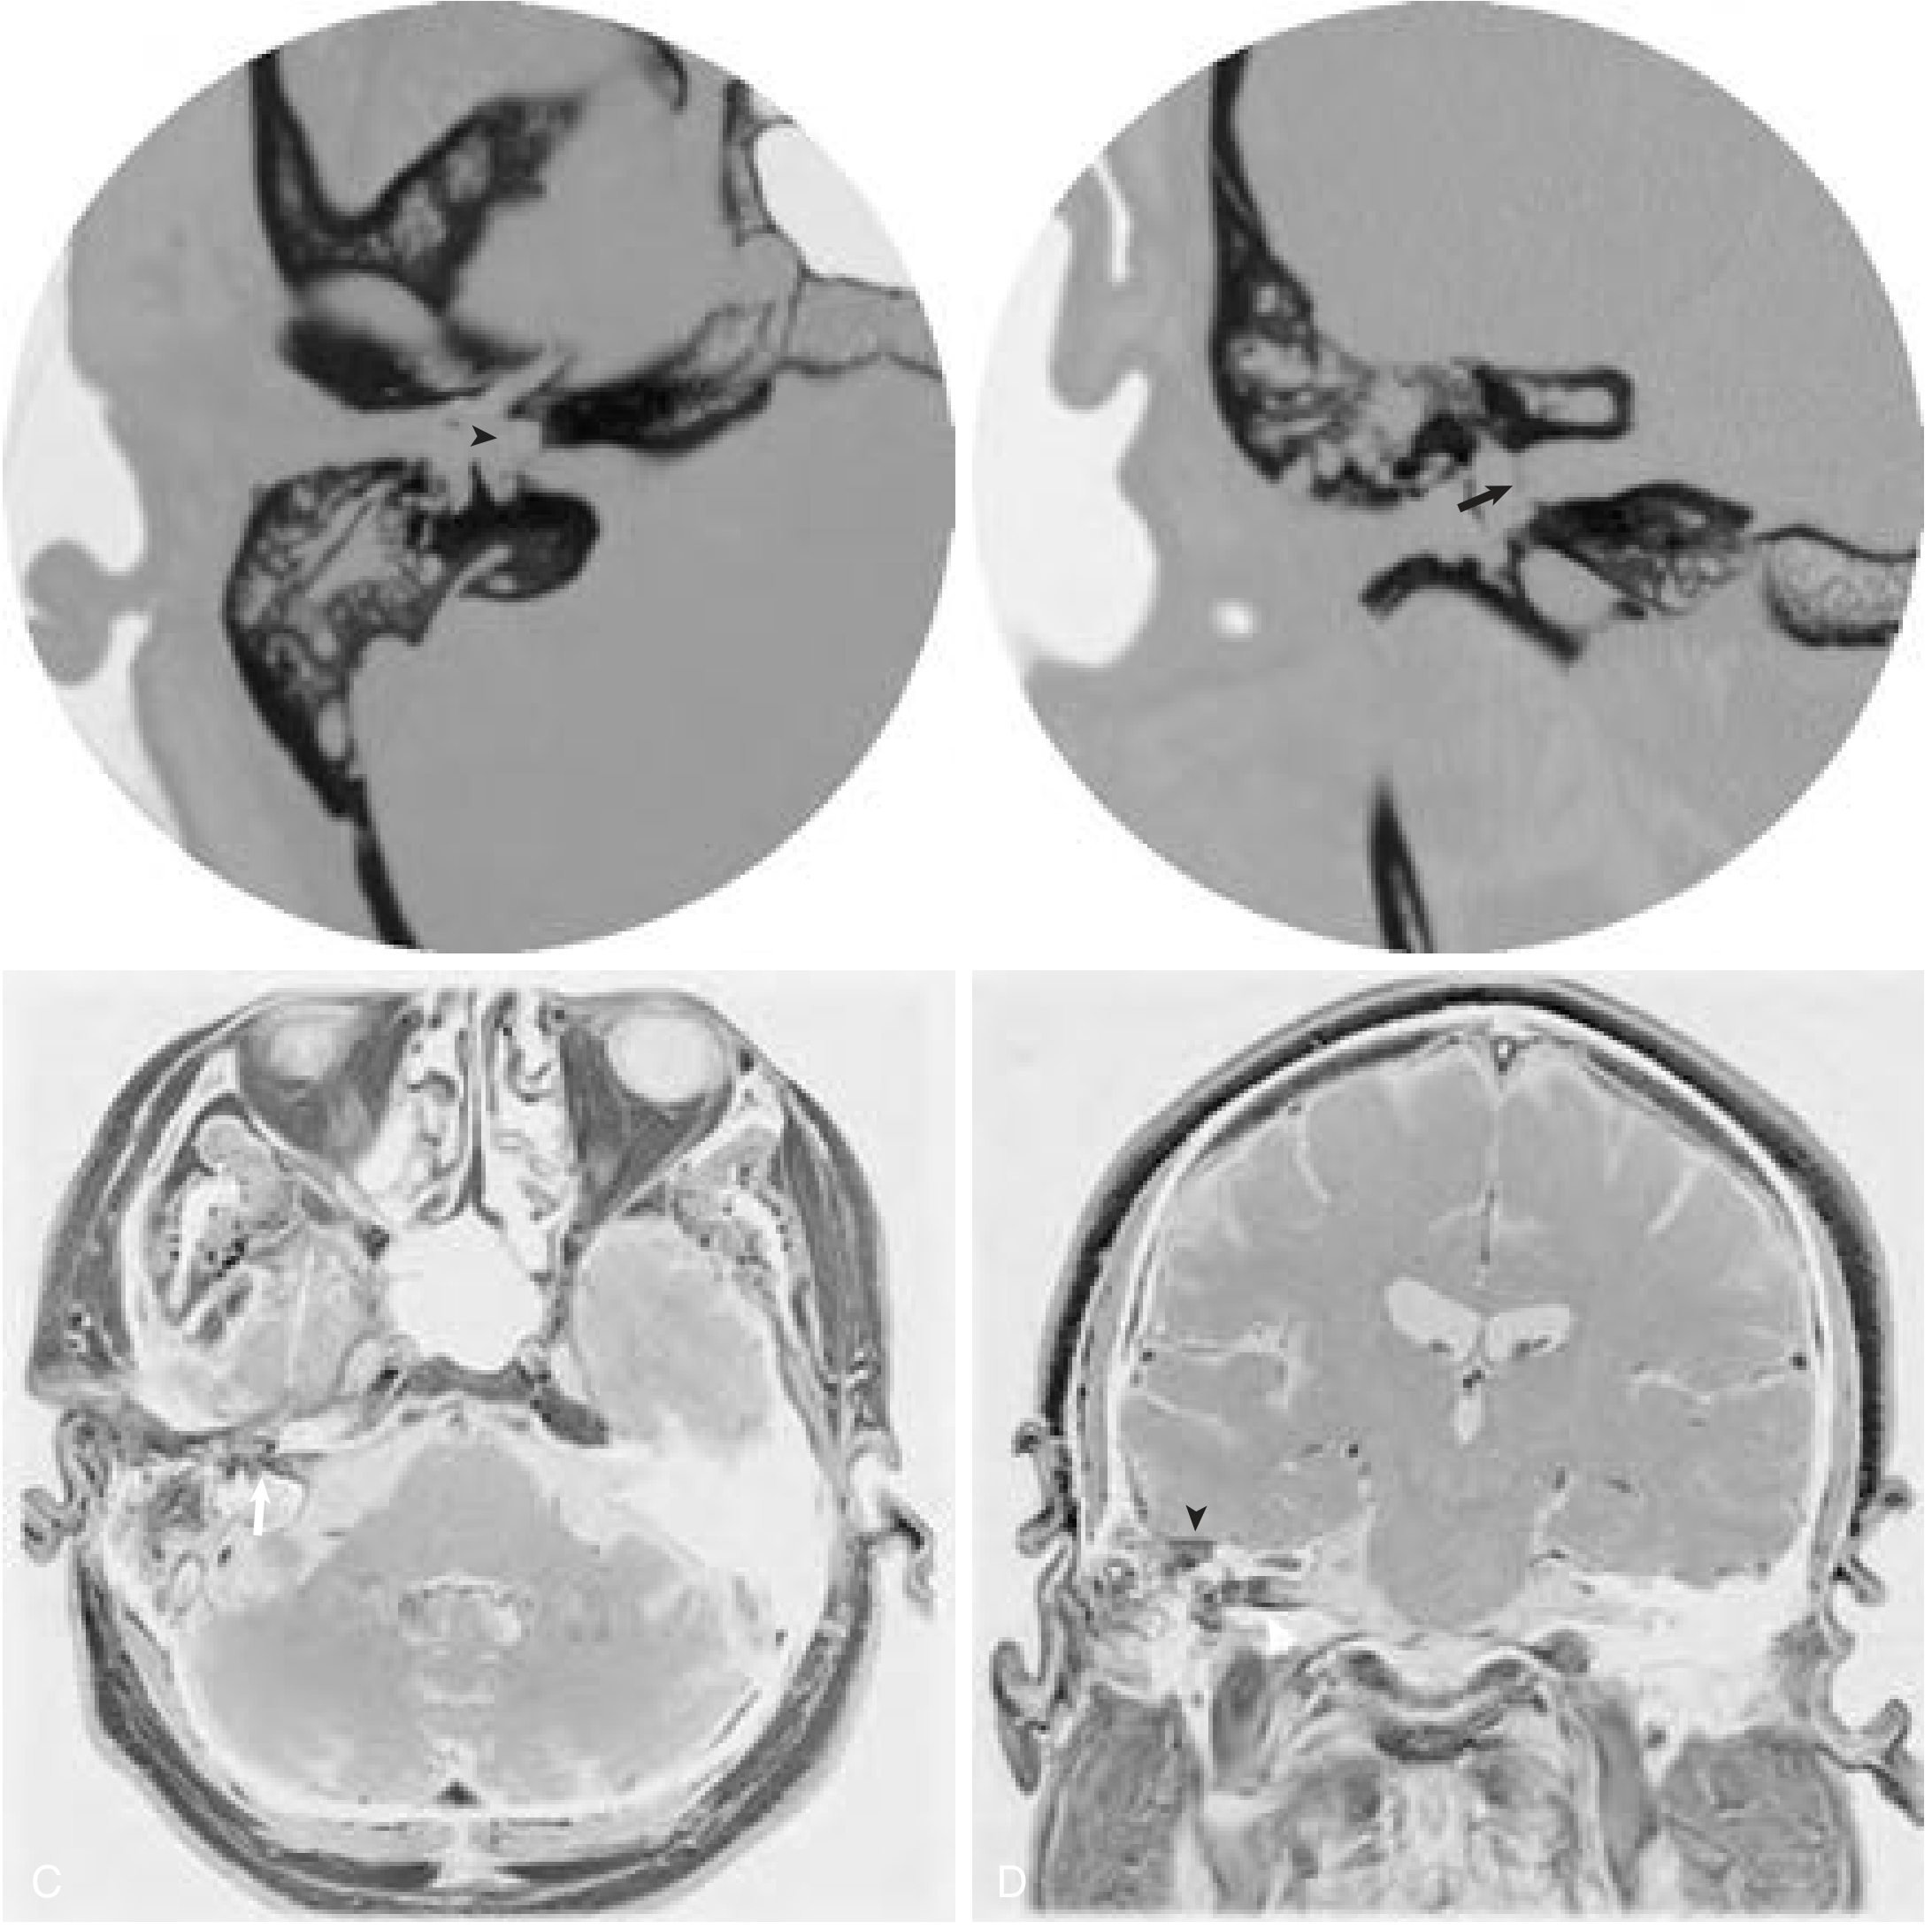

Imaging of acute suppurative labyrinthitis

CT and MRI findings in acute suppurative labyrinthitis: opacified mastoid, erosion of vestibule and IAC fundus, enhancement of middle ear/vestibule/IAC, and temporal lobe dural enhancement.

MRI of temporal lobe abscess from otogenic source

Left mastoiditis with petrous apicitis, temporal lobe abscess with enhancing capsule, and surrounding edema on T1/T2 MRI.